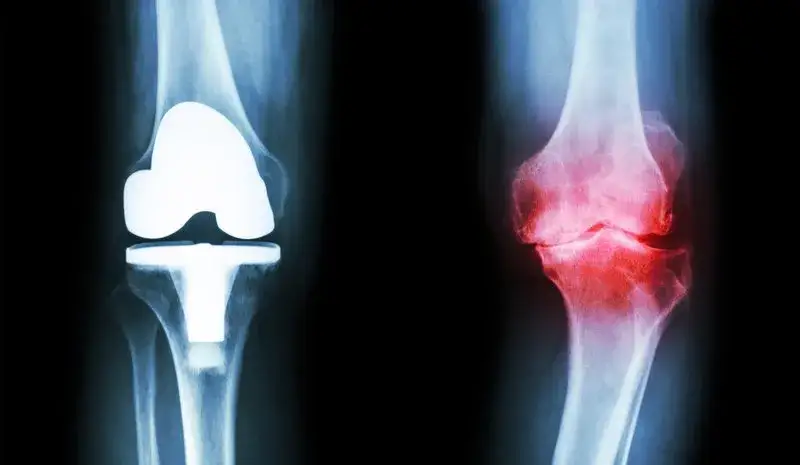

- Zdjęcia RTG stawu kolanowego